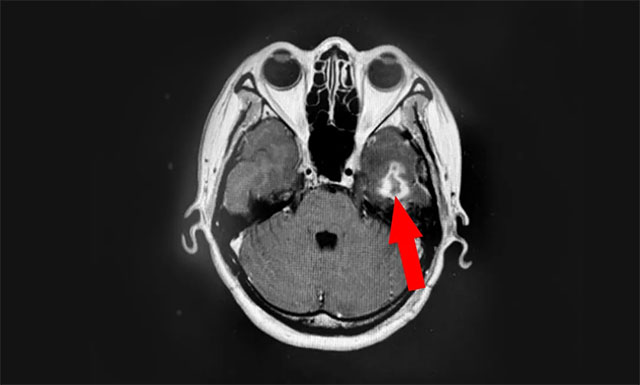

近期,患者为寻求进一步治疗,来到上海蓝十字脑科医院。医院肿瘤科(放疗)头部伽玛刀组主任陈琦及医生团队结合患者病情变化,为汤女士行立体定向穿刺引流联合伽玛刀治疗。经一段时间住院恢复后复查,病灶占位较前进一步缩小,肿瘤进展得到了较好地控制,目前已顺利出院。

▲ 伽玛刀治疗后复查,可见病灶占位明显缩小

陈琦主任表示,与开放性手术、全脑放疗及化疗等其他治疗方案相比,立体定向穿刺引流联合伽玛刀治疗,具有侵袭性更小、对患者条件要求低的优势,治疗后患者神经系统症状可迅速减轻,从而改善生存质量。是目前不开颅治疗囊性脑转移瘤较好的选择。